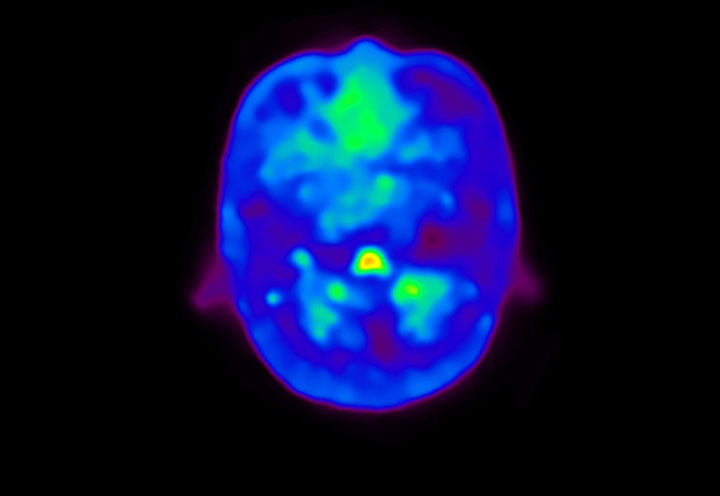

Head / Case4 : Amyloid

Coronal

Courtesy : Kindai University Hospital

- Imaging protocol

- Injected dose: 3.21 MBq/kg, 18F-Flutemetamol

- Uptake time: 100 minutes

- Scan time: 20 minutes